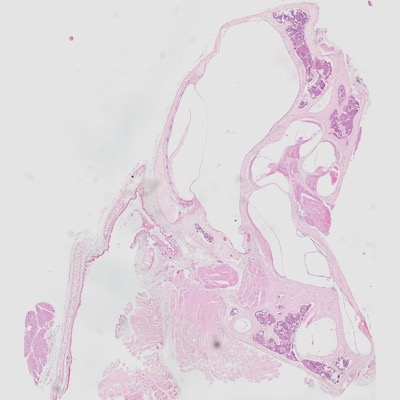

Oído